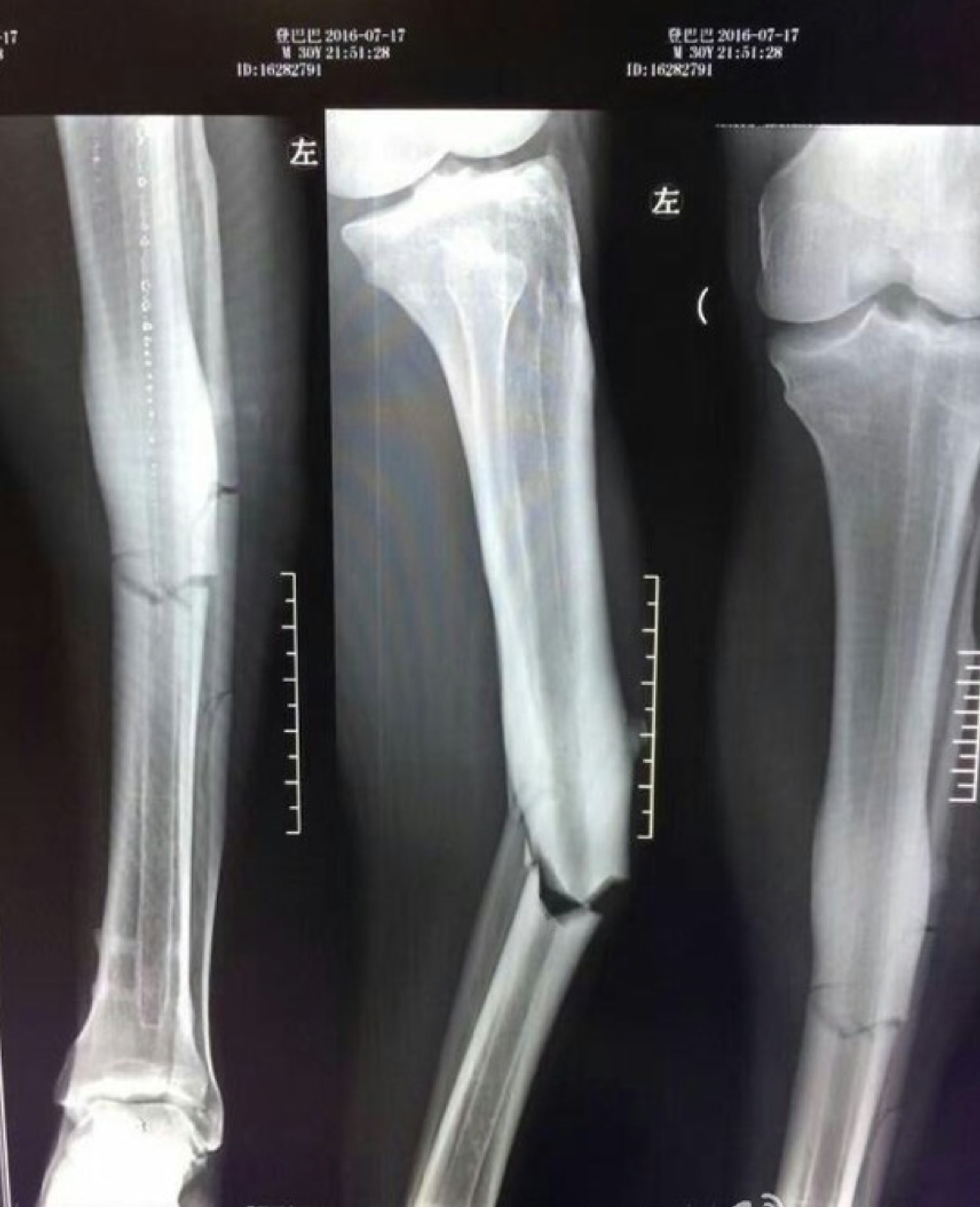

Një fotografim i këmbës së thyer së Demba Ba, ka shpallur ish-sulmuesin e Chelseat tashmë tetë muaj jashtë fushës.

31-vjeçari senegalez pësoi një lëndim në pjesën e dytë, ku Shanghai Shenhua fitoi me rezultat 2-1 ndaj rivalëve të hidhur të Shanghai SIPG.

Pas thyerjes së këmbës, Ba u dërgua në spital dhe u zgjua me dhimbje të mëdha pas katër orëve, pas marrjes së anestezionit të përgjithshëm.